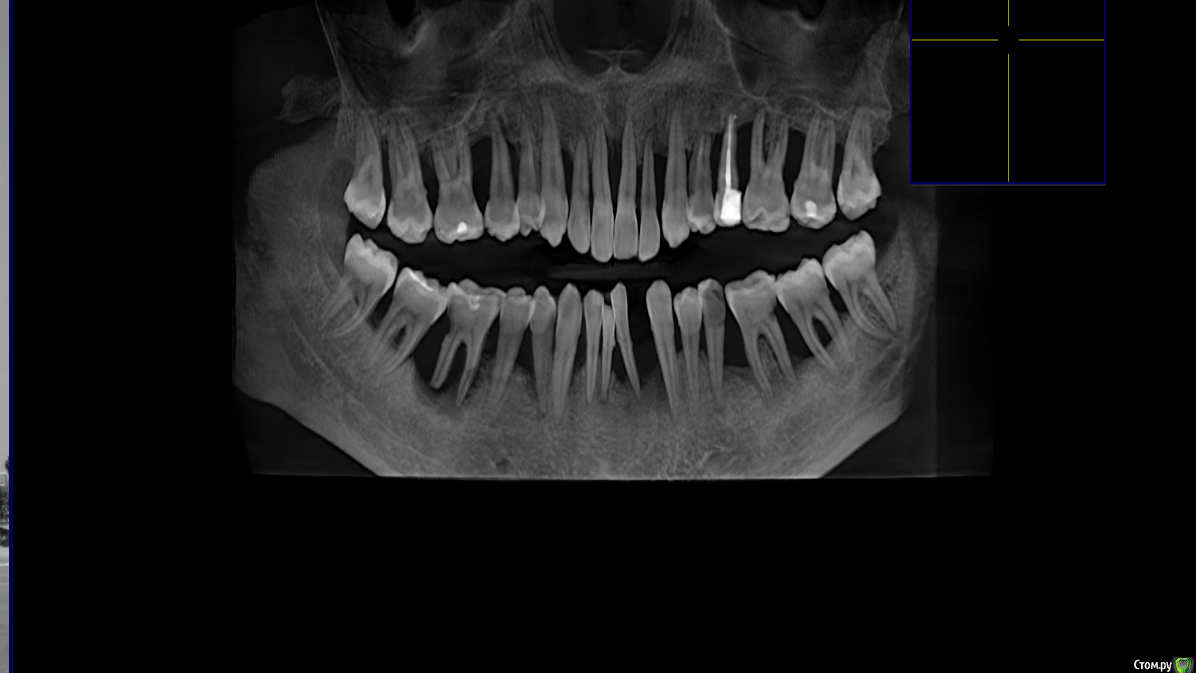

andrey75 Опубликовано 7 октября, 2020 Поделиться Опубликовано 7 октября, 2020 Что можно сделать в данном случае? Стою на распутье. Ссылка на комментарий

andrey75 Опубликовано 7 октября, 2020 Автор Поделиться Опубликовано 7 октября, 2020 Перспектива ? С чего начать,и как закончить. Ссылка на комментарий

Большой Зеленый Опубликовано 7 октября, 2020 Поделиться Опубликовано 7 октября, 2020 Все грустно .С зубами в перспективе придется прощаться. Ссылка на комментарий

It'sGeorgy Опубликовано 7 октября, 2020 Поделиться Опубликовано 7 октября, 2020 Я бы начал с выяснения соответствия между запросами и финансовыми возможностями пациента. Затем, понять причину такой значительной костной потери. 1 Ссылка на комментарий

Bier Опубликовано 7 октября, 2020 Поделиться Опубликовано 7 октября, 2020 все на 4х, что тут думать то? 1 Ссылка на комментарий

andrey75 Опубликовано 8 октября, 2020 Автор Поделиться Опубликовано 8 октября, 2020 все на 4х, что тут думать то?И верх. ч и нижняя ч. Ортопедия мультиюниты,Балка,Акриловые зубы Ссылка на комментарий

Дмитрий М Опубликовано 11 октября, 2020 Поделиться Опубликовано 11 октября, 2020 ОПГ.pngнаходка для пародонтолога ))) Ссылка на комментарий